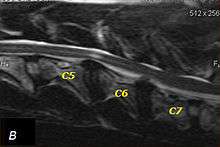

MRI of wobbler's in the neck of a dog

The disease tends to be gradually progressive. Symptoms such as weakness, ataxia, and dragging of the toes start in the rear legs. Dogs often have a crouching stance with a downward flexed neck. The disease progresses to the front legs, but the symptoms are less severe. Neck pain is sometimes seen. Symptoms are usually gradual in onset, but may progress rapidly following trauma.[6] X-rays may show misaligned vertebrae and narrow disk spaces, but it is not as effective as a myelogram, which reveals stenosis of the vertebral canal. Magnetic resonance imaging has been shown to be more effective at showing the location, nature, and severity of spinal cord compression than a myelogram.[7] Treatment is either medical to control the symptoms, usually with corticosteroids and cage rest, or surgical to correct the spinal cord compression. The prognosis is guarded in either case. Surgery may fully correct the problem, but it is technically difficult and relapses may occur. Types of surgery include ventral decompression of the spinal cord (ventral slot technique), dorsal decompression, and vertebral stabilization.[8] One study showed no significant advantage to any of the common spinal cord decompression procedures.[9] Another study showed that electroacupuncture may be a successful treatment for Wobbler disease.[10] A new surgical treatment using a proprietary medical device has been deveolped for dogs with disc-associated wobbler disease. It implants an artificial disc (cervical arthroplasty) in place of the affected disc space.[11]